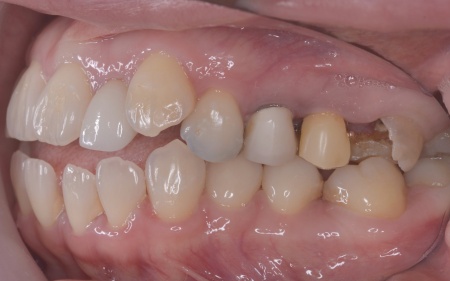

| カウンセリング | 拝見したところ、左下と右上の歯はともに大きな虫歯があり、歯だけでなく被せ物を支える土台の部分にも影響が及んでいました。

さらに、ほかの歯に入っている詰め物や被せ物の周囲にも、過去に治療した部分に再び虫歯ができる二次カリエスが複数見つかりました。 また、噛み合わせを確認したところ、奥歯で噛み合わせた際に上下の前歯が当たらず隙間ができる開咬(かいこう)が認められました。 実際に患者様の場合も、特定の歯に長期間強い力がかかり続けたことで歯や修復物の破損、さらには口腔内全体のトラブルにつながった可能性が高いと考えられました。 修復治療が必要でしたがこの噛み合わせの問題を改善しないまま行うと、治療した歯に再び過度な力が加わって被せ物の破損・脱離や虫歯の再発を招くリスクが高まります。 |